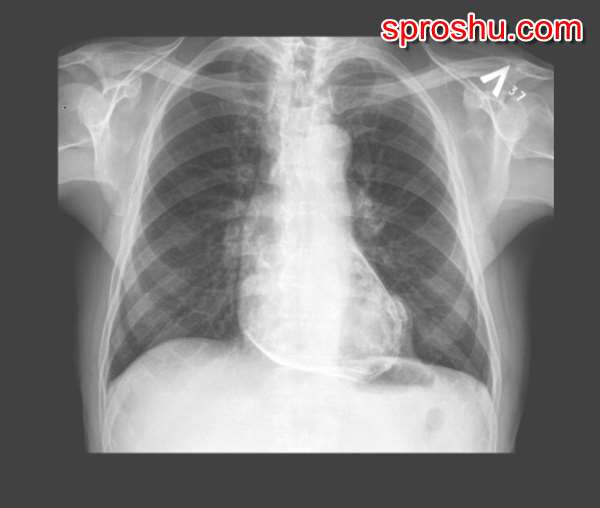

Перикардит бывает острый и хронический. Острый при своевременном лечении может быть благополучно вылечен. Но процесс может перейти в хроническую форму, перикард при этом постепенно утолщается, огрубевает, нередко в нём начинает откладываться кальций, и перикард может даже окостенеть. У сердца появляется "панцирь". Такое состояние и называется "панцирное сердце". Можете посмотреть, как это выглядит на рентгеновском снимке:

Понятно, что отложения кальция становятся очень хорошо на нём видны. Сердце при этом не может ни нормально расширяться и наполняться, сдавленное таким изменённым перикардом, ни сокращаться и выталкивать кровь в аорту (справедливости ради, работа сердца начинает нарушаться намного раньше, когда перикард изменяется под воздействием воспаления, но тогда эти изменения вполне вероятно обратимы).